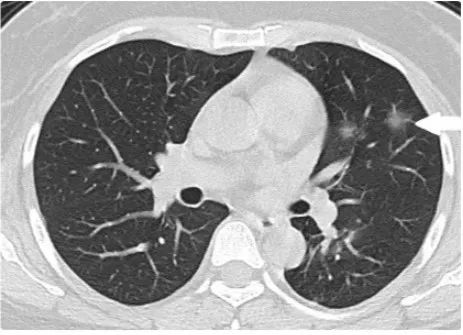

1. COVID-19病变早期CT表现

病变局限,斑片状、亚段或节段性分布为主。病变常于外1/3肺野、胸膜下分布。表现为单发或多发磨玻璃样密度(GGO)结节状、斑片或片状影,伴或不伴小叶间隔增厚为主,其内可见空气支气管征和血管增粗表现。

图1 49男性干咳2d,SARS-CoV-2核酸检测阳性,HRCT示双肺可见斑片状磨玻璃样密度增高影,境界欠清